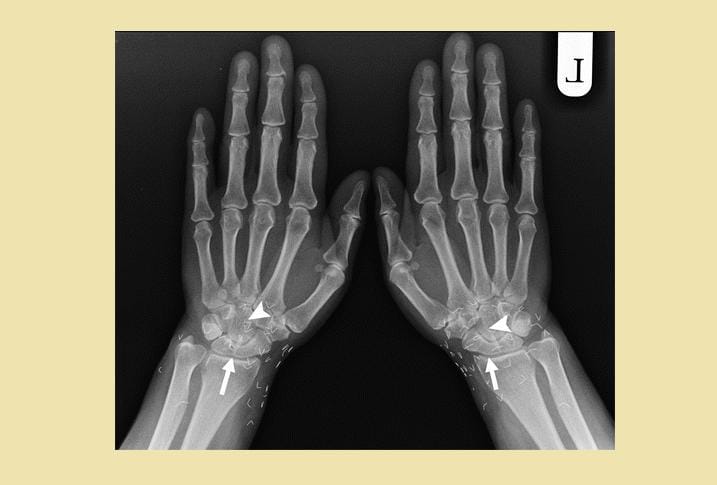

1. Ratusan susuk terlihat jelas lewat hasil foto sinar-X

Dalam unggahannya itu, Tasqia menuliskan bahwa ia sedang menangani seorang pasien berusia 55 tahun yang ingin melakukan X-ray atau sinar-X. Tak disangka, hasil foto sinar-X pasien tersebut memperlihatkan ratusan atau bahkan ribuan benda asing berbentuk seperti jarum yang bersarang pada tubuh pasiennya itu. Tasqia pun menyebut benda tersebut sebagai susuk. Sangking banyaknya, Tasqia pun tak tahu pasti berapa jumlah susuk yang ada pada bagian tubuh pasiennya itu.

Menurut Tasqia, dalam bahasa Inggris, ia menyebut susuk sebagai charm needle. Hal ini lantaran bentuknya yang seperti jarum. Susuk juga menurut Tasqia bisa berubah posisi ketika dilakukan foto sinar-X lagi.

5. Umumnya ditemukan di sekitar kepala

Ketika ditanya biasanya susuk banyak ditemukan di area tubuh yang mana, Tasqia menjawab bahwa susuk bisa dimasukkan di mana saja. Namun, biasanya banyak ditemukan di sekitar kepala dan sisanya ada sekitar area kaki hingga payudara.

"LMAOOOO yess bisa dimana ajaaa cuma emang umumnya di daerah kepala, sisanya bisa di kaki tangan, perut, dada, payudara, dll," tulisnya.